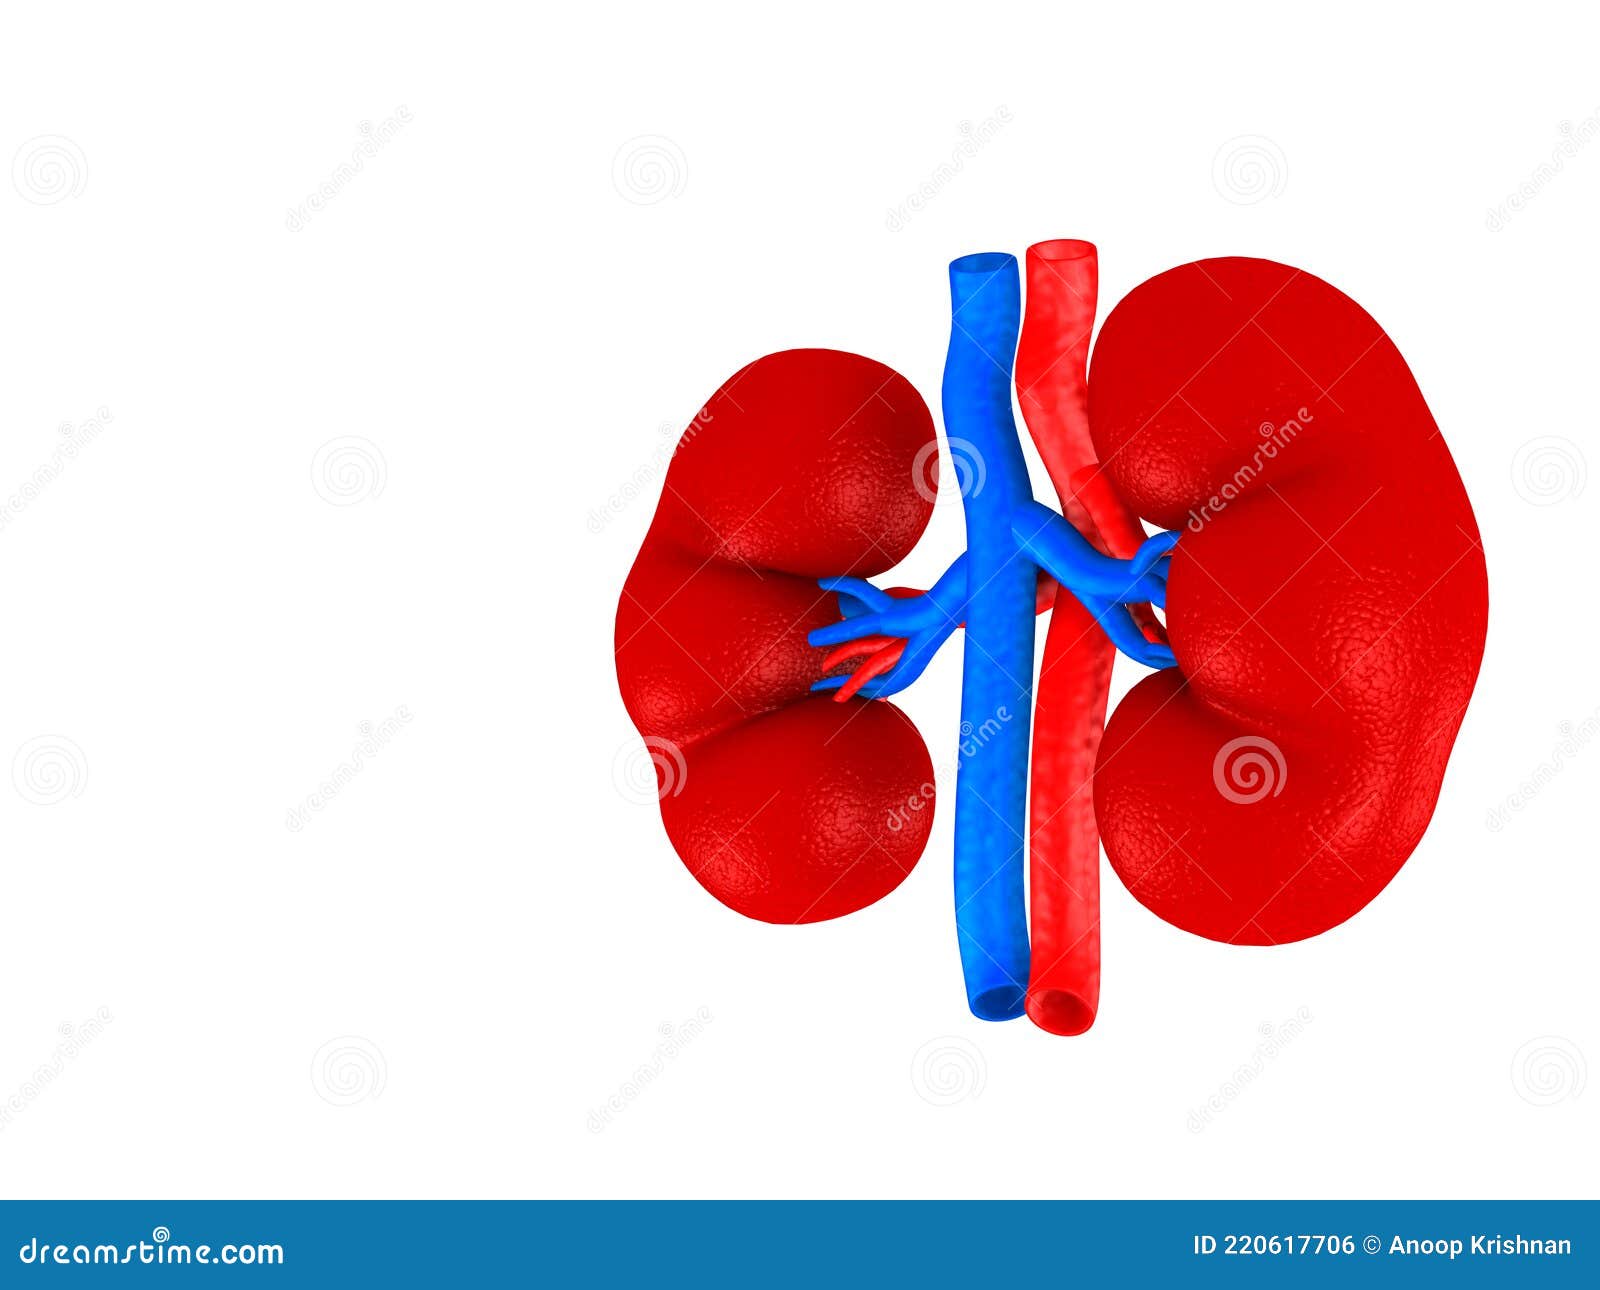

Строение почек человека: Фото и описание